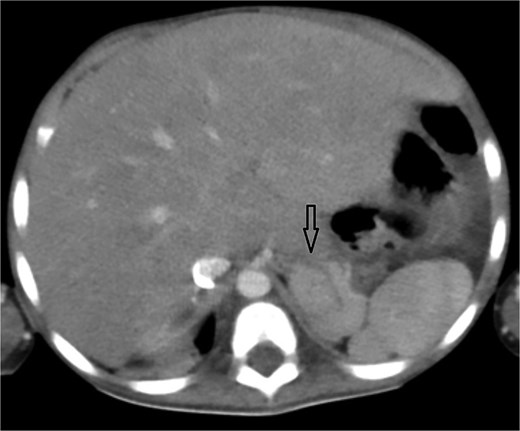

Axial abdominal CT showing central liver and polysplenism, compatible with left isomerism.

Urgent transthoracic echocardiography demonstrated a large echodense mass in the right hemithorax, compression of the right atrium and reduced flow through the right-sided shunt. Computed tomography angiography (CTA) confirmed a massive saccular pseudoaneurysm (≈8 × 7 × 6 cm) arising from the anastomosis between the right subclavian artery and the mBTTS graft, completely thrombosed without active contrast extravasation (Fig. 1). There was complete thrombotic occlusion of the right pulmonary artery, right lung collapse due to extrinsic compression and right lower-lobe consolidation consistent with pneumonia (Fig. 2). CTA also revealed left isomerism with central liver and polysplenism (Fig. 3) and a horseshoe kidney (Fig. 4), suggesting a previously unrecognized polymalformative syndrome.